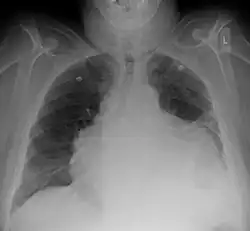

| A 2D echo transthoracic echocardiogram of pericardial effusion. The "swinging" heart. | |

ECG: may present with sinus tachycardia, low voltage QRS as well as electrical alternans.[2] Due to the fluid accumulation around the heart, the heart is further away from the chest leads, which leads to the low voltage QRS. Electrical alternans signifies the up-and-down change of the QRS amplitude with every beat due to the heart swinging in the fluid (as displayed in the ultrasound image in the introduction) .[1] These three findings together should raise suspicion for impending hemodynamic instability associated with cardiac tamponade.

Echocardiogram (ultrasound): when pericardial effusion is suspected, echocardiography usually confirms the diagnosis and allows assessment of the size, location and signs of hemodynamic instability.[4] A transthoracic echocardiogram (TTE) is usually sufficient to evaluate pericardial effusion and it may also help distinguish pericardial effusion from pleural effusion and MI. Most pericardial effusions appear as an anechoic area (black or without an echo) between the visceral and the parietal membrane.[1] Complex or malignant effusions are more heterogeneous in appearance, meaning they may have variations in echo on ultrasound.[5] TTE can also differentiate pericardial effusion based on the size. Although it's difficult to define size classifications because they vary with institutions, most commonly they are as follows: small <10, moderate 10–20, large >20.[5] An echocardiogram is urgently needed for evaluation when there is concern for hemodynamic compromise, a rapidly developing effusion or history of recent cardiac surgery/procedures.[1]